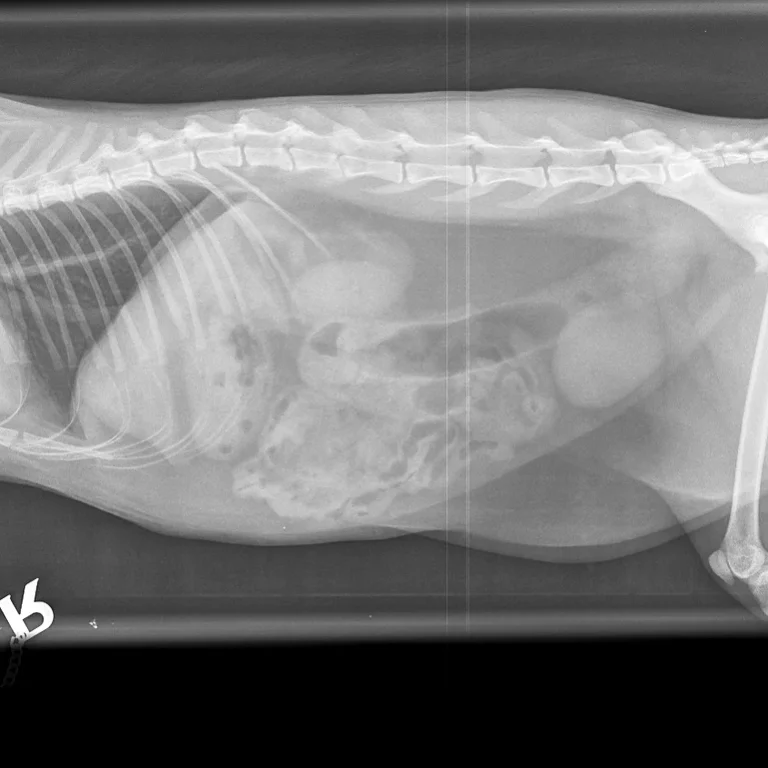

Dental radiographs are one of the most important diagnostic tools available to a veterinary dentist. They allow the internal anatomy of the teeth, the roots and the bone that surrounds the roots to be examined.